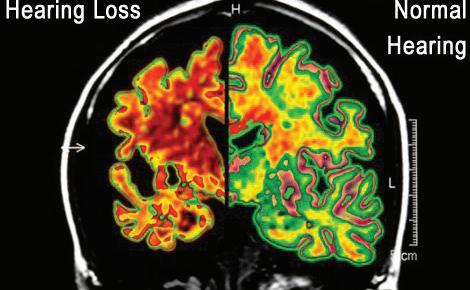

Photo from Metro Creative Connection Hospitalization rates are slowing improving after skyrocketing during the fall due to the combined impacts of Respiratory syncytial virus (RSV), influenza, and COVID variants. Contributed photos The OBAB volunteers filled this trailer and more with trash collected during the cleanup effort.

A8 | FRIDAY, JANUARY 20, 2023 THE WORLD ARE YOU AT RISK? All of the tests are FREE! compares to normal hearing. otoscope* be excess wax. Miracle-Ear technology yourself! QUIZ TO FIND OUT... the when restauquestions, there’s good news! moment. Call us today. “Hearing loss, left untreated can lead to serious problems such as loneliness and isolation.” Mention Code: Special Notice State Employees You may qualify for a hearing aid benefit up to $4,000 every 4 years. Call for eligibility status. Individual experiences will vary depending on severity of loss, accuracy of evaluation by our 30 days of completion of fitting in satisfactory condition for a full refund. North Bend 1938 Newmark St North Bend, OR 97459 (541)264-7539 Alzheimer’s Disease According to a new study by Johns Medicine and the National Institute hearing loss are much more likely to disease. People with severe hearing loss, more likely to develop dementia Free Public Service! Free Free Your hearing will and you will be shown Your ears will be to determine if your In-store demonstration so you can hear Free Have you noticed your ability “The more hearing loss likelihood of developing disease. Hearing aids could by improving the -2011 Study by Johns Hopkins University School IS IT TIME FOR A HEARING Y Do you feel that people mumble or do not speak clearly? Do you turn the TV up louder than others need to? Do family or friends get frustrated when you ask them to repeat themselves? If you’ve answered “Yes” Miracle-Ear can Hearing tests are always free. Hearing test is an audiometric test to determine Consultant, proper fit, and the ability to adjust to amplification. Visit N hearing disease. disease. IS Y Hearing Alzheimer’s Disease and Dementia - ARE YOU AT RISK? According to a new study by Johns Hopkins University School of Medicine and the National Institute on Aging, men and women with hearing loss are much more likely to develop dementia and Alzheimer’s disease. People with severe hearing loss, the study reports, were 5 times Free Public Service! 3-Days Only! All of the tests are FREE! Free Free Your hearing will be electronically tested* and you will be shown how your hearing compares to normal hearing. Your ears will be examined with a video otoscope* to determine if your hearing problem may just be excess wax. In-store demonstration of the newest Miracle-Ear technology so you can hear the improvement for yourself! Free Have you noticed a change in your ability to remember? “The more hearing loss you have, the greater the likelihood of developing dementia or Alzheimer’s disease. Hearing aids could delay or prevent dementia by improving the patient’s hearing.” -2011 Study by Johns Hopkins University School of Medicine and the National Institute of Aging IS IT TIME FOR A HEARING TEST? TAKE THIS QUIZ TO FIND OUT... Y Do you feel that people mumble or do not speak clearly? Do you turn the TV up louder than others need to? Do family or friends get frustrated when you ask them to repeat themselves? Do you have trouble understanding the voices of women or small children when they are speaking? Is it hard to follow the conversation in noisy places like parties, crowded restaurants or family get-togethers? If you’ve answered “Yes” to any one of these questions, there’s good news! Miracle-Ear can help! Don’t wait another moment. Call us today. “Hearing loss, left untreated can lead to serious problems such as Mention Code: aid benefit up to $4,000 every 4 Hearing tests are always free. Hearing test is an audiometric test to determine proper amplification needs only. Hearing Aids do not restore natural hearing. Individual experiences will vary depending on severity of loss, accuracy of evaluation by our Consultant, proper fit, and the ability to adjust to amplification. Pursuant to terms of your purchase agreement, the aids must be returned within 30 days of completion of fitting in satisfactory condition for a full refund. Visit us Online at: www.miracle-ear.com Florence 2775 Hwy 101, Ste. B Florence, OR 97439 (541)201-8129 North Bend 1938 Newmark St North Bend, OR 97459 (541)264-7539 N Y N Alzheimer’s Disease and Dementia - ARE YOU AT RISK? Free Public Service! 3-Days Only! All of the tests are FREE! Free Free Your hearing will be electronically tested* and you will be shown how your hearing compares to normal hearing. Your ears will be examined with a video otoscope* to determine if your hearing problem may just be excess wax. In-store demonstration of the newest Miracle-Ear technology so you can hear the improvement for yourself! Free Have you noticed a change in your ability to remember? “The more hearing loss you have, the greater the likelihood of developing dementia or Alzheimer’s disease. Hearing aids could delay or prevent dementia by improving the patient’s hearing.” -2011 Study by Johns Hopkins University School of Medicine and the National Institute of Aging IS IT TIME FOR A HEARING TEST? TAKE THIS QUIZ TO FIND OUT... Y Do you feel that people mumble or do not speak clearly? Do you turn the TV up louder than others need to? Do family or friends get frustrated when you ask them to repeat themselves? Do you have trouble understanding the voices of women or small children when they are speaking? Is it hard to follow the conversation in noisy places like parties, crowded restaurants or family get-togethers? If you’ve answered “Yes” to any one of these questions, there’s good news! Miracle-Ear can help! Don’t wait another moment. Call us today. “Hearing loss, left untreated can Mention Code: Hearing tests are always free. Hearing test is an audiometric test to determine proper amplification needs only. Hearing Aids do not restore natural hearing. Individual experiences will vary depending on severity of loss, accuracy of evaluation by our Consultant, proper fit, and the ability to adjust to amplification. Pursuant to terms of your purchase agreement, the aids must be returned within 30 days of completion of fitting in satisfactory condition for a full refund. Visit us Online at: www.miracle-ear.com Florence 2775 Hwy 101, Ste. B Florence, OR 97439 (541)201-8129 North Bend 1938 Newmark St North Bend, OR 97459 (541)264-7539 N Y N Don’t Wait! Call and make your 23JanDementia 5-Days Only! Alzheimer’s Disease and Dementia - ARE YOU AT RISK? According to a new study by Johns Hopkins University School of Medicine and the National Institute on Aging, men and women with hearing loss are much more likely to develop dementia and Alzheimer’s disease. People with severe hearing loss, the study reports, were 5 times more likely to develop dementia than those with normal hearing. Free Public Service! 3-Days Only! All of the tests are FREE! Free Free Your hearing will be electronically tested* and you will be shown how your hearing compares to normal hearing. Your ears will be examined with a video otoscope* to determine if your hearing problem may just be excess wax. In-store demonstration of the newest Miracle-Ear technology so you can hear the improvement for yourself! Free Have you noticed a change in your ability to remember? “The more hearing loss you have, the greater the likelihood of developing dementia or Alzheimer’s disease. Hearing aids could delay or prevent dementia by improving the patient’s hearing.” -2011 Study by Johns Hopkins University School of Medicine and the National Institute of Aging IS IT TIME FOR A HEARING TEST? TAKE THIS QUIZ TO FIND OUT... Y Do you feel that people mumble or do not speak clearly? Do you turn the TV up louder than others need to? Do family or friends get frustrated when you ask them to repeat themselves? Do you have trouble understanding the voices of women or small children when they are speaking? Is it hard to follow the conversation in noisy places like parties, crowded restaurants or family get-togethers? If you’ve answered “Yes” to any one of these questions, there’s good news! Miracle-Ear can help! Don’t wait another moment. Call us today. “Hearing loss, left untreated can lead to serious problems such as loneliness and isolation.” Mention Code: Special Notice State Employees You may qualify for a hearing aid benefit up to $4,000 every 4 years. Call for eligibility status. Hearing tests are always free. Hearing test is an audiometric test to determine proper amplification needs only. Hearing Aids do not restore natural hearing. Individual experiences will vary depending on severity of loss, accuracy of evaluation by our Consultant, proper fit, and the ability to adjust to amplification. Pursuant to terms of your purchase agreement, the aids must be returned within 30 days of completion of fitting in satisfactory condition for a full refund. Visit us Online at: www.miracle-ear.com Florence 2775 Hwy 101, Ste. B Florence, OR 97439 (541)201-8129 North Bend 1938 Newmark St North Bend, OR 97459 (541)264-7539 N Y N  LED Lighting  Remodeling  Fire Alarm Systems  Telephone Lines TV and Computer Cabling Circuit Breaker Panel Repair RESIDENTIAL-COMMERCIAL-INDUSTRIAL aON DEMAND aON TIME aON BUDGET North Bend 541-756-0581 Bandon 541-347-3066 reeseelectric.com FULL SERVICE ELECTRICIANS CCB#23563 24 Hour Emergency Service Contributed photo During the winter months, the Oregon Coast, especially in the Cape Arago area, can provide amazing views of storms that hit Oregon.